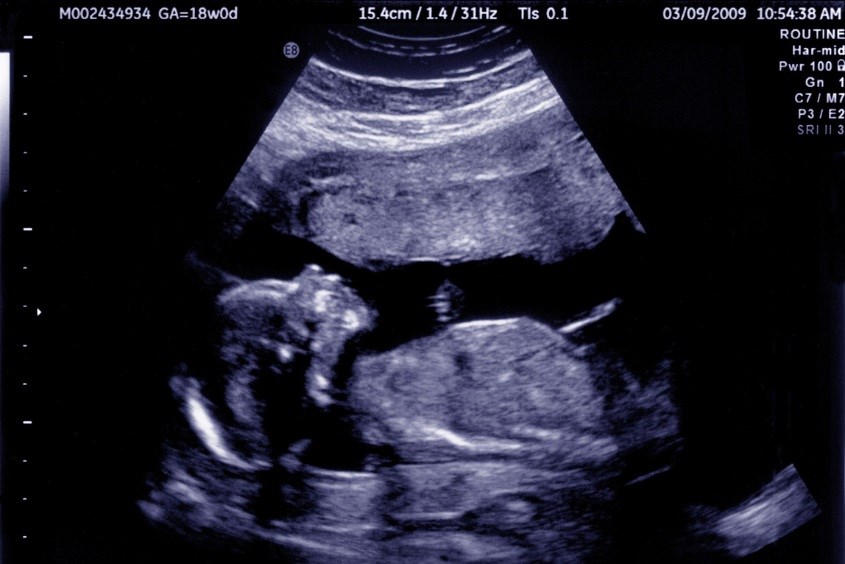

Đây là phương pháp xác định ngôi thai hiện đại và có độ chính xác tương đối cao. Mỗi thai nhi sẽ có thời điểm bắt đầu xoay ngôi thai khác nhau. Mốc thời gian xoay ngôi trung bình của hầu hết là từ tuần 28 trở đi.

Ngôi thai sẽ ổn định ở tuần thứ 35 của thai kỳ và đây cũng là thời điểm vàng để siêu âm xác định ngôi thai. Bên cạnh cho mẹ biết ngôi thai là thuận hay ngược, bác sĩ còn cung cấp cho mẹ những thông tin quan trọng khác của thai nhi như: Cân nặng và hình dáng của thai nhi, mức độ phát triển các cơ quan của thai nhi, tình trạng nước ối.

Phương pháp siêu âm để xác định ngôi thai trong bụng mẹ